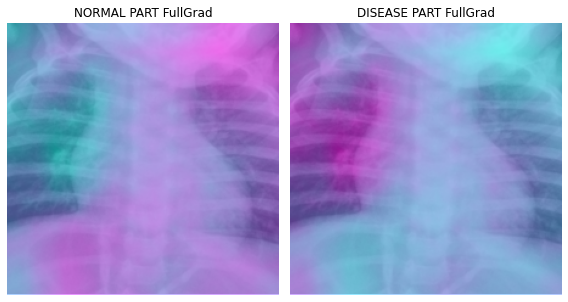

fig, (ax1,ax2) = plt.subplots(1,2)

dls.train.decode((x,))[0].squeeze().show(ax=ax1)

ax1.imshow(-cam_fullgrad.squeeze(),alpha=0.5,extent=(0,224,224,0),interpolation='bilinear',cmap='cool')

ax1.set_title("NORMAL PART FullGrad")

#

dls.train.decode((x,))[0].squeeze().show(ax=ax2)

ax2.imshow(cam_fullgrad.squeeze(),alpha=0.5,extent=(0,224,224,0),interpolation='bilinear',cmap='cool')

ax2.set_title("DISEASE PART FullGrad")

fig.set_figwidth(8)

fig.set_figheight(8)

fig.tight_layout()